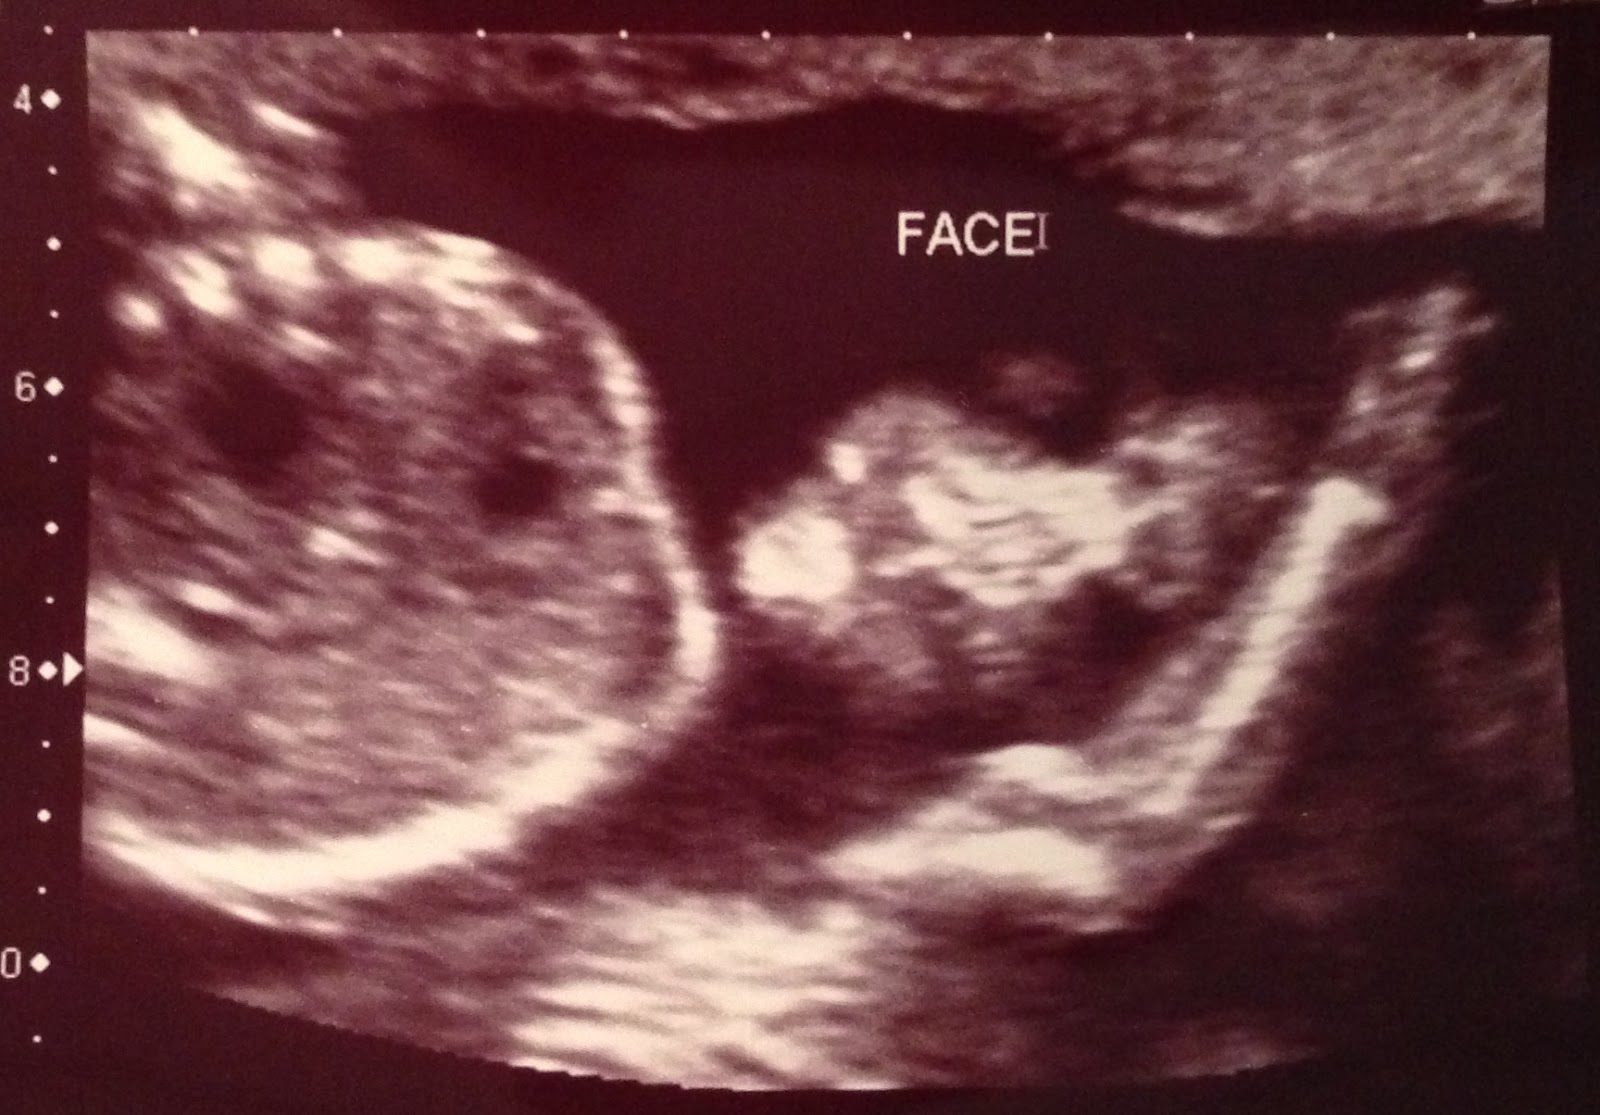

How To Prepare For Baby At 20 Weeks. You might be able to borrow baby clothes, furniture, and strollers from friends and family members with older children. Celebrate by doing something special for you—whether it’s a nice dinner, a new shirt or watching your favorite movie. Around 20 weeks, you�ll have an ultrasound, so the doctor can assess your baby�s growth and make sure all the organs are developing properly. Your baby’s skin thickens and develops layers under the vernix during the 20th week of pregnancy.

At 20 weeks pregnant, i had hope for my baby. At 20 weeks pregnant, the baby is as big as a banana/sweet potato. The first is generally offered at around 12. It�s becoming increasingly uncommon for pregnant women to have their very first ultrasound at 20 weeks, though this used to be the first opportunity for most pregnant mums to be able to see their baby inside the uterus. By 20 weeks most of your baby has developed such that screening of the organs is possible to assess for abnormalities.

Create a baby registry for your baby shower to let friends and family know which items would be the most helpful as you prepare for your baby’s arrival. Schedule and prepare for your first prenatal visit,. The scan can take a minimum of 45 minutes and sometimes up to an hour. With babylist, you can add anything from any store to your registry, and even items like help and favors for meals, dog walking and more. The aim of this examination is to make sure your foetus is developing properly, and to rule out certain conditions that can be detected during an ultrasound.

At 20 weeks pregnant, the baby is as big as a banana/sweet potato. This is likely when you can. Around 20 weeks, you�ll have an ultrasound, so the doctor can assess your baby�s growth and make sure all the organs are developing properly. You could always start with the shorter duration and increase it as your pregnancy progresses. This ultrasound uses high frequency sound waves that generate a.